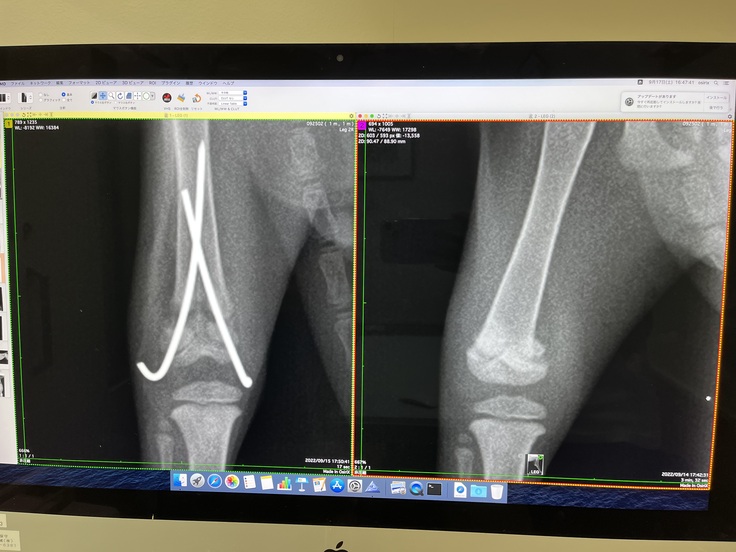

(↓左:手術後クロスピンで骨を正常な位置に戻した様子、右:手術前)

右大腿骨骨折部分にクロスピンを入れて元の位置に戻す手術を行いました。